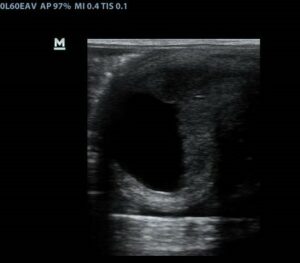

Nanango Country Vet – Horses – Pregnant Mare Scan